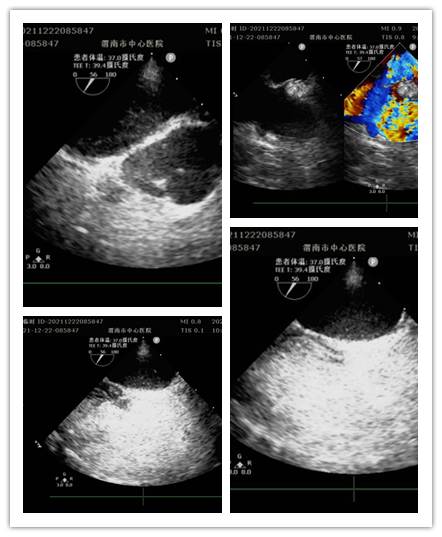

12月22日上午,乐鱼在线登录入口超声科门诊完成全市首例经食管超声心动图。这是继完成30例术中经食管超声心动图之后首次在门诊进行。此项检查填补了渭南市超声诊疗空白,标志着医院心血管诊疗技术迈向新台阶。

患者女性,13岁,因间断眩晕1年,加重伴头痛20余天就诊于医院全科医学科。住院期间,行经胸超声右心声学造影提示存在心内分流,为进一步明确心脏疾病,行经食管超声心动图检查。检查前,超声科杨玉萍医师对患者充分评估,与刘晓晖主任共同商定患者检查方案,进行充分准备。为保障小患者安全,全科医学科副主任医师苗娟妮、心脏外科副主任姜永红及团队全程参与。在多名医护人员的通力协作下,成功为患者行经食管超声检查。检查过程顺利,患者无不良反应,最终明确超声诊断,为患者进一步治疗提供了有力依据。

经食管超声心动图检查是将超声探头插入食管,直接贴在心脏的后方,从后向前观察心脏、血管和血流动力学情况,避免了气体及脂肪的干扰。加之食道超声的探头频率高于普通经胸超声探头,所以能扩大心脏的扫查范围,提高图像质量及细微分辨率。主要运用于术前评估、术中监测、术后复查,尤其是对经胸超声心动图检查成像困难或有关结构显示不清,致使诊断难以明确的各种心脏或大血管疾病患者,能更加准确地诊断心脏细小病变及疑难疾病。特别是能有效评估房颤患者血栓形成的危险性并作为可靠依据,对房颤治疗前期评估具有重要意义。